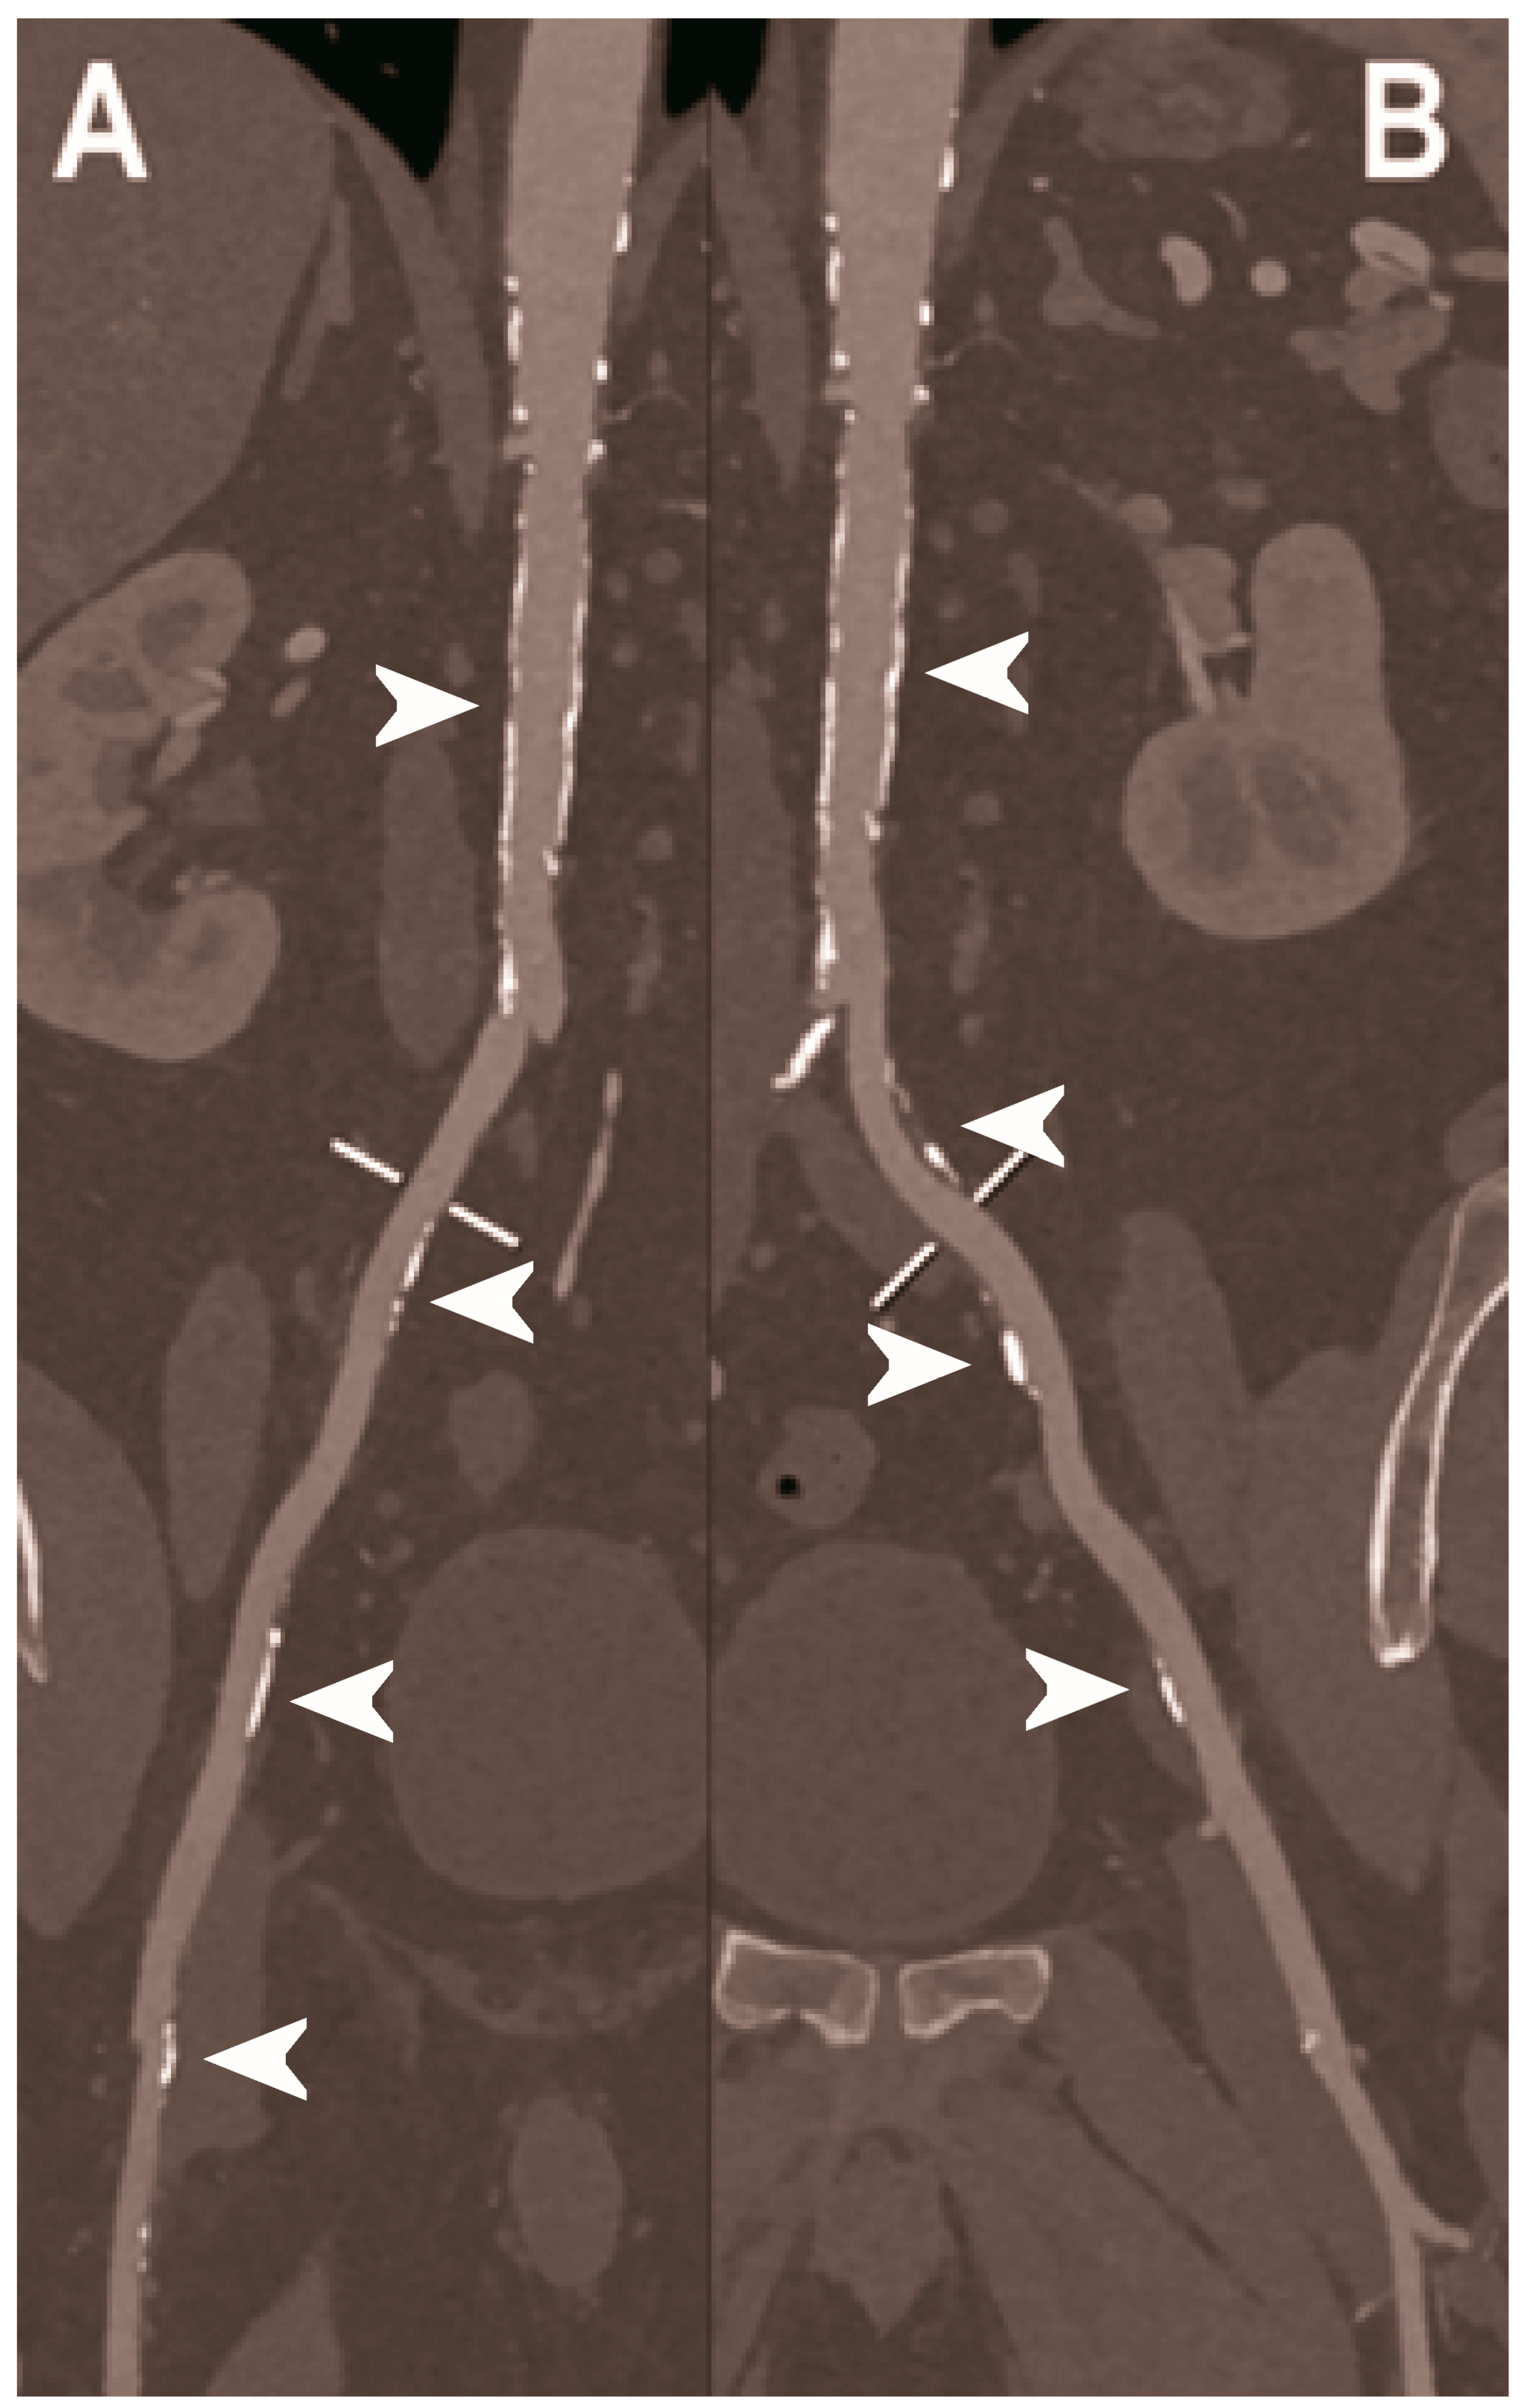

| Dangelmaier et al. 2018 [111] | In vitro phantom (abdominal aortic aneurysm phantom filled with iodine, gadolinium, or calcium). | Ability of PCCT in combination with a dual contrast agent injection to capture endoleak dynamics and effectively distinct leaking contrast media from intra-aneurysmatic calcifications, thereby allowing for a significant reduction of radiation exposure. |

| Sigovan et al. 2019 [112] |

|

|

- Dangelmaier, J.; Bar-Ness, D.; Daerr, H.; Muenzel, D.; Si-Mohamed, S.; Ehn, S.; Fingerle, A.A.; Kimm, M.A.; Kopp, F.K.; Boussel, L.; et al. Experimental feasibility of spectral photon-counting computed tomography with two contrast agents for the detection of endoleaks following endovascular aortic repair. Eur. Radiol. 2018, 28, 3318–3325. [Google Scholar] [CrossRef]

- Sigovan, M.; Si-Mohamed, S.; Bar-Ness, D.; Mitchell, J.; Langlois, J.B.; Coulon, P.; Roessl, E.; Blevis, I.; Rokni, M.; Rioufol, G.; et al. Feasibility of improving vascular imaging in the presence of metallic stents using spectral photon counting CT and K-edge imaging. Sci. Rep. 2019, 9, 19850. [Google Scholar] [CrossRef] [PubMed] [Green Version]